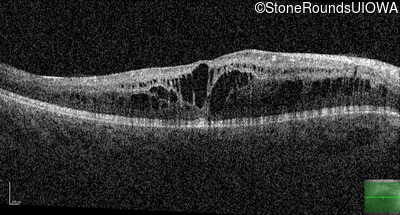

Optical Coherence Tomography - Left - 20/50 -2

Exemplar / OCT Stack

OCT Stack